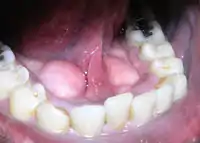

Tórus mandibularis é um crescimento ósseo na mandíbula, ao longo da superfície mais próxima à língua. Estão habitualmente presentes perto aos pré-molares. Em noventa por cento dos casos, há um toro em ambos os lados.

A prevalência da mandíbula varia entre 5 - 40 por cento e são menos comuns do que o crescimento ósseo no palato, conhecido como tórus palatino. São mais comuns nos países da Ásia, e ligeiramente mais comum em indivíduos do sexo masculino. Nos Estados Unidos, a prevalência é de 7% - 10% da população com resultados semelhantes entre negros e brancos.